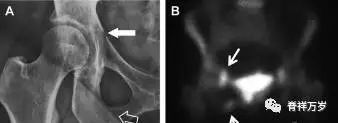

股骨头骨折

股骨头骨折常与髋关节脱位有关。需要注意的是那些既不是因剪力损伤也不是因直接*力暴**作用造成的骨折。这些类型的骨折可能十分轻微。提倡应用 CT 检查,不仅可诊断骨折,而且能评估关节内骨折碎片的位置(图 5)。

图 5 股骨颈骨折伴髋关节脱位。A 股骨头上外侧轮廓缺失(空箭头)注意嵌入上方关节间隙的骨折碎片(黑色箭头)B 冠状位 CT 多维重建(MPR)证实骨软骨碎片(白色箭头)和关节上方的另一个碎片(空箭头)